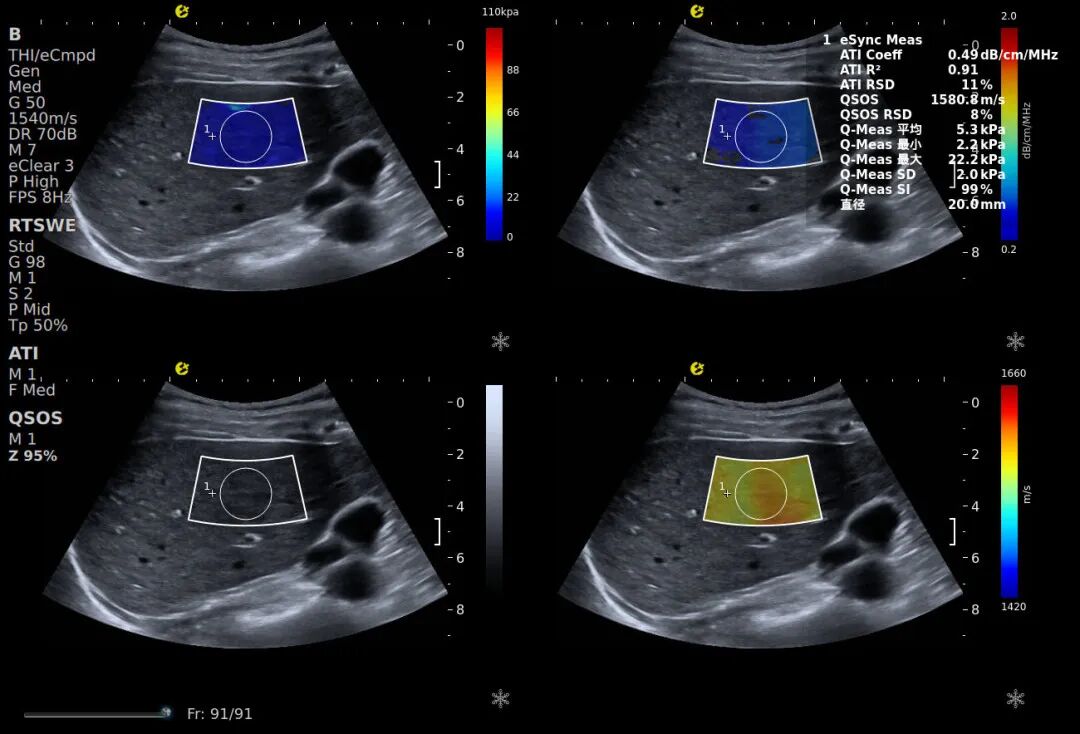

在这样的背景下,慢性肝病的早筛早诊成为护肝关键,而传统诊断方式的局限性却日益凸显。为破解这一临床困境,助力全国爱肝日“早筛防重症”的核心诉求,E超无创诊断设备凭借其技术创新,为慢性肝病无创筛查提供了全新解决方案。该设备区别于传统单一维度检测设备,E超构建了“硬度+脂肪+密实度+黏性”的四维定量评估体系,结合当前慢性肝病无创诊断的核心趋势(多参数联合评估),通过E成像(RTSWE®可精准量化肝脏硬度)、声衰减系数(ATI™)、声速定量(QSOS®)、黏弹性定量(QVisco™)四大参数的有机融合,实现了对肝脏病变的全方位解码,覆盖早期病变发现和肝纤维化、脂肪浸润等核心病变类型。

声速定量成像-QSOS®

作为早期损伤“探测器”的QSOS®声速定量技术,通过捕捉肝脏实质内声波传播速度的细微变化,能在纤维化萌芽阶段就发出预警,弥补了传统技术对早期肝损伤的漏判短板。